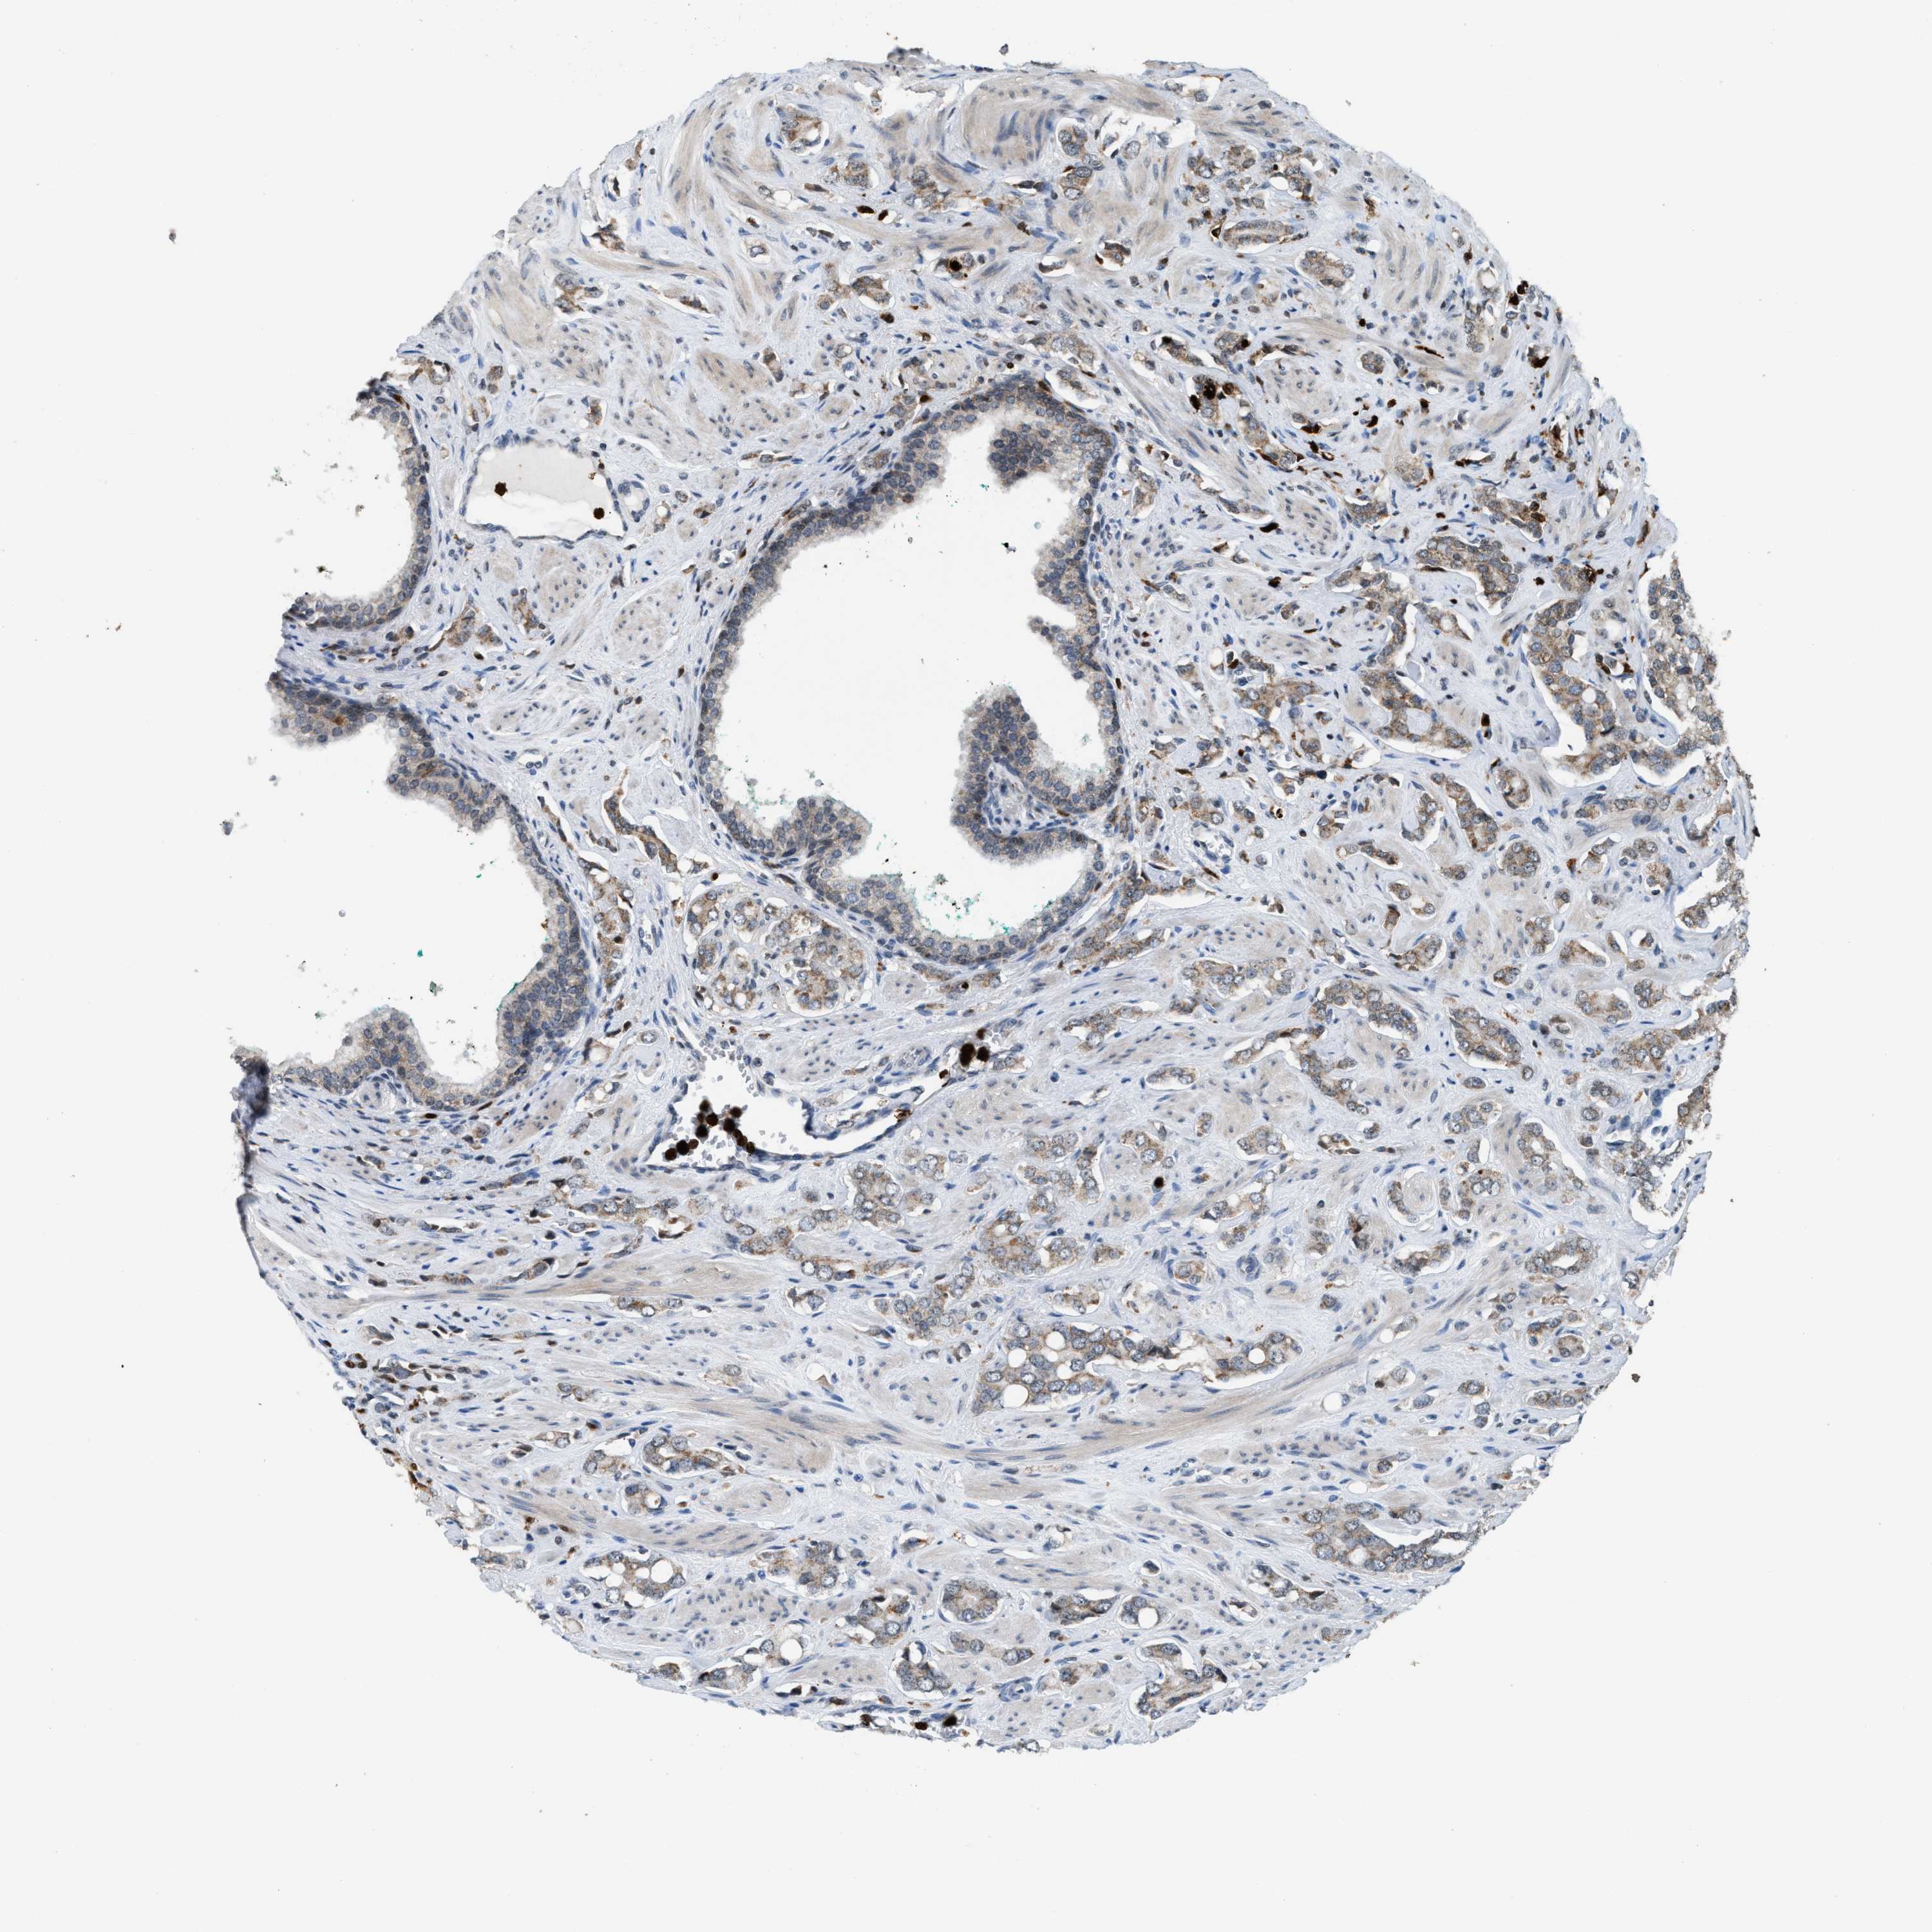

PROSTATE CANCER - Protein expressioni

A mouse-over function shows sample information and annotation data. Click on an image to view it in a full screen mode. Samples can be filtered based on level of antibody staining by selecting one or several of the following categories: high, medium, low and not detected. The assay and annotation is described here.

Note that samples used for immunohistochemistry by the Human Protein Atlas do not correspond to samples in the TCGA dataset.

Antibody stainingi

Antibody staining in the annotated cell types in the current human tissue is reported as not detected, low, medium, or high, based on conventional immunohistochemistry profiling in selected tissues. This score is based on the combination of the staining intensity and fraction of stained cells.

Each image is clickable and will lead to virtual microscopy that enables deeper exploration of all samples and also displays staining intensity scores, fraction scores and subcellular localization as well as patient and tissue information for each sample.

Antibody HPA022470

Antibody HPA031079

Staining

High

Medium

Low

Not detected

Intensity

Strong

Moderate

Weak

Negative

Quantity

>75%

75%-25%

<25%

None

Location

Nuclear

Cytoplasmic/membranous

Cytoplasmic/membranous,nuclear

Adenocarcinoma, High grade

Adenocarcinoma, Low grade